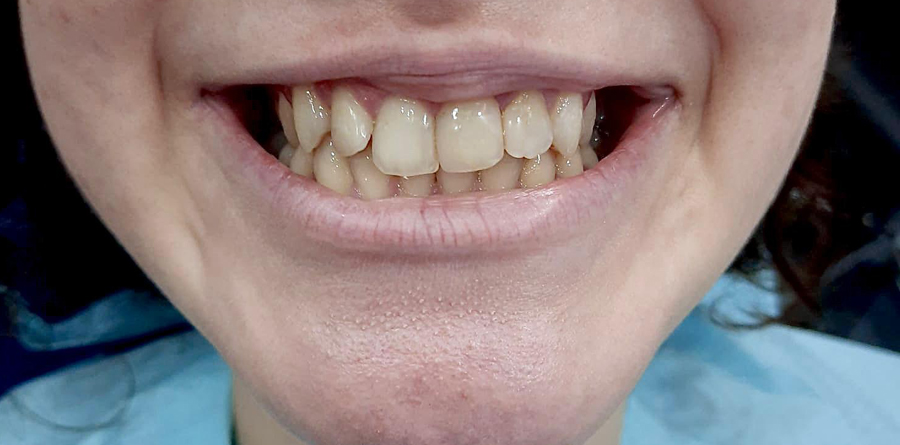

Vorher Nachher